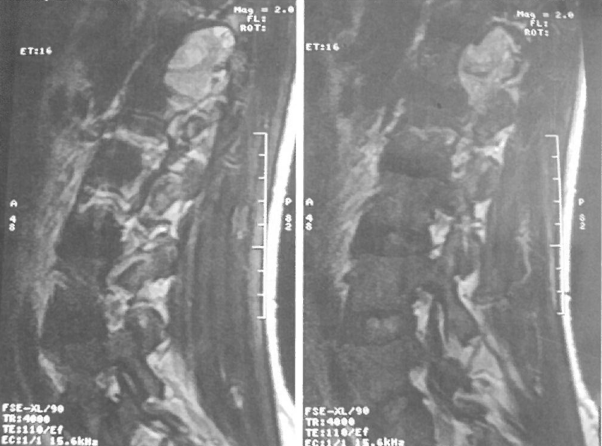

美国看病机构爱诺美康了解到,MRI检查可以看到在L1水平有一累及椎管内外的明显强化的肿块(图)。手术采用的是单纯后路切除,术中切除椎板及小关节后暴露肿瘤(图3)。

图2 MRI显示累及L1-2椎间孔的椎旁肿块。